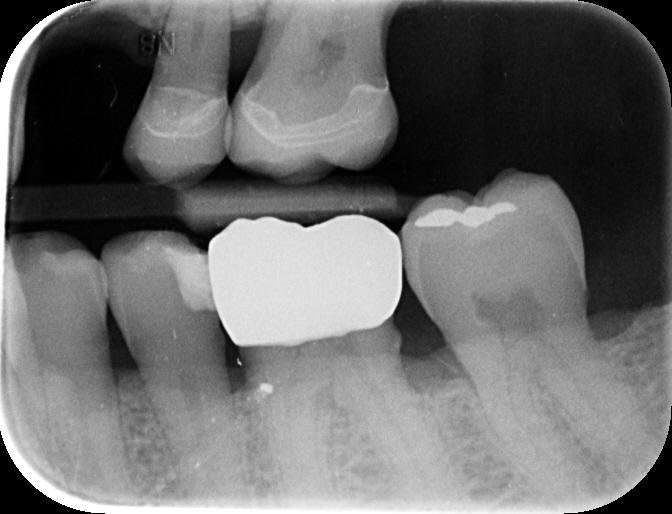

A radiographic assessment confirmed the proper integration and positioning of the implant.

The successful treatment outcome can be attributed to digital dentistry: planning, precise execution, and patient-centered approach facilitated by the digital workflow.

By leveraging advanced technologies like 3Shape TRIOS, Implant Studio, and TRIOS Design Studio, I delivered a high-quality, customized implant-supported restoration that met the patient's functional, aesthetic, and emotional needs.